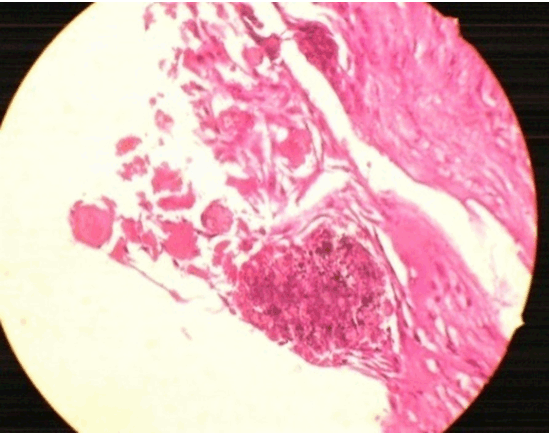

Figure 5: Histopathological section showing amorphous structures with well-defined borders without nucleus resembling ghost cells, and the eosinophilic dentinoid like material and basophilic round to irregular calcified masses are also seen.

Calcifying odontogenic cysts are usually non neoplastic with cystic features but, sometimes they appear as solid mass with neoplastic features. The solid lesions are named dentinogenic ghost cell tumor (DGCT), epithelial odontogenic ghost cell tumor (EOGCT). There has been confusion in classification and nomenclature of the lesion [6], because of its diversified histopathological features.